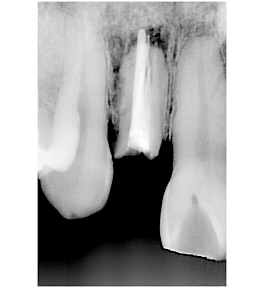

右上の歯の前から2番目を抜歯し、即時にインプラントを施した前歯部・審美領域の治療

- 被せ物が脱離した右上2は歯根破折をしており、保存不可能と判断されたため抜歯と同時のインプラント埋入を計画。抜歯と同時にインプラント埋入。そのインプラントの生着を待って上部構造の装着を行なった